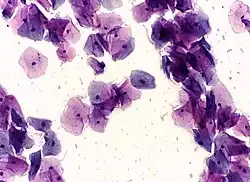

High-grade squamous intraepithelial lesion

Pap tests commonly examine epithelial abnormalities, such as metaplasia, dysplasia, or borderline changes, all of which may be indicative of CIN. Nuclei will stain dark blue, squamous cells will stain green and keratinised cells will stain pink/ orange. Koilocytes may be observed where there is some dyskaryosis (of epithelium). The nucleus in koilocytes is typically irregular, indicating possible cause for concern; requiring further confirmatory screens and tests.